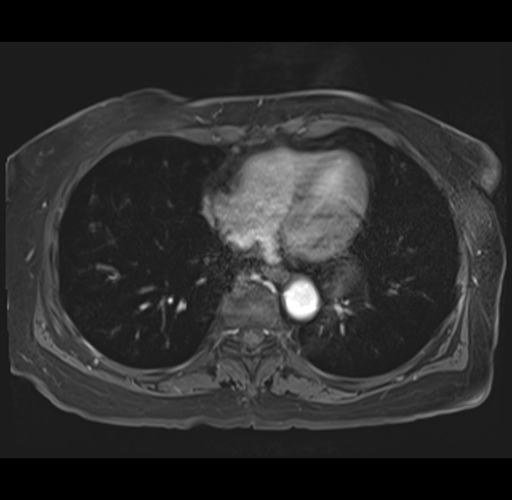

MRI T1